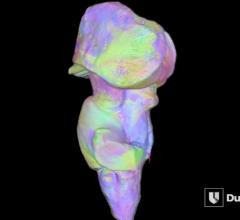

August 13, 2015 —In an effort to demonstrate how 3-D printing can help better interpret medical imaging, Philips teamed ...

August 13, 2015